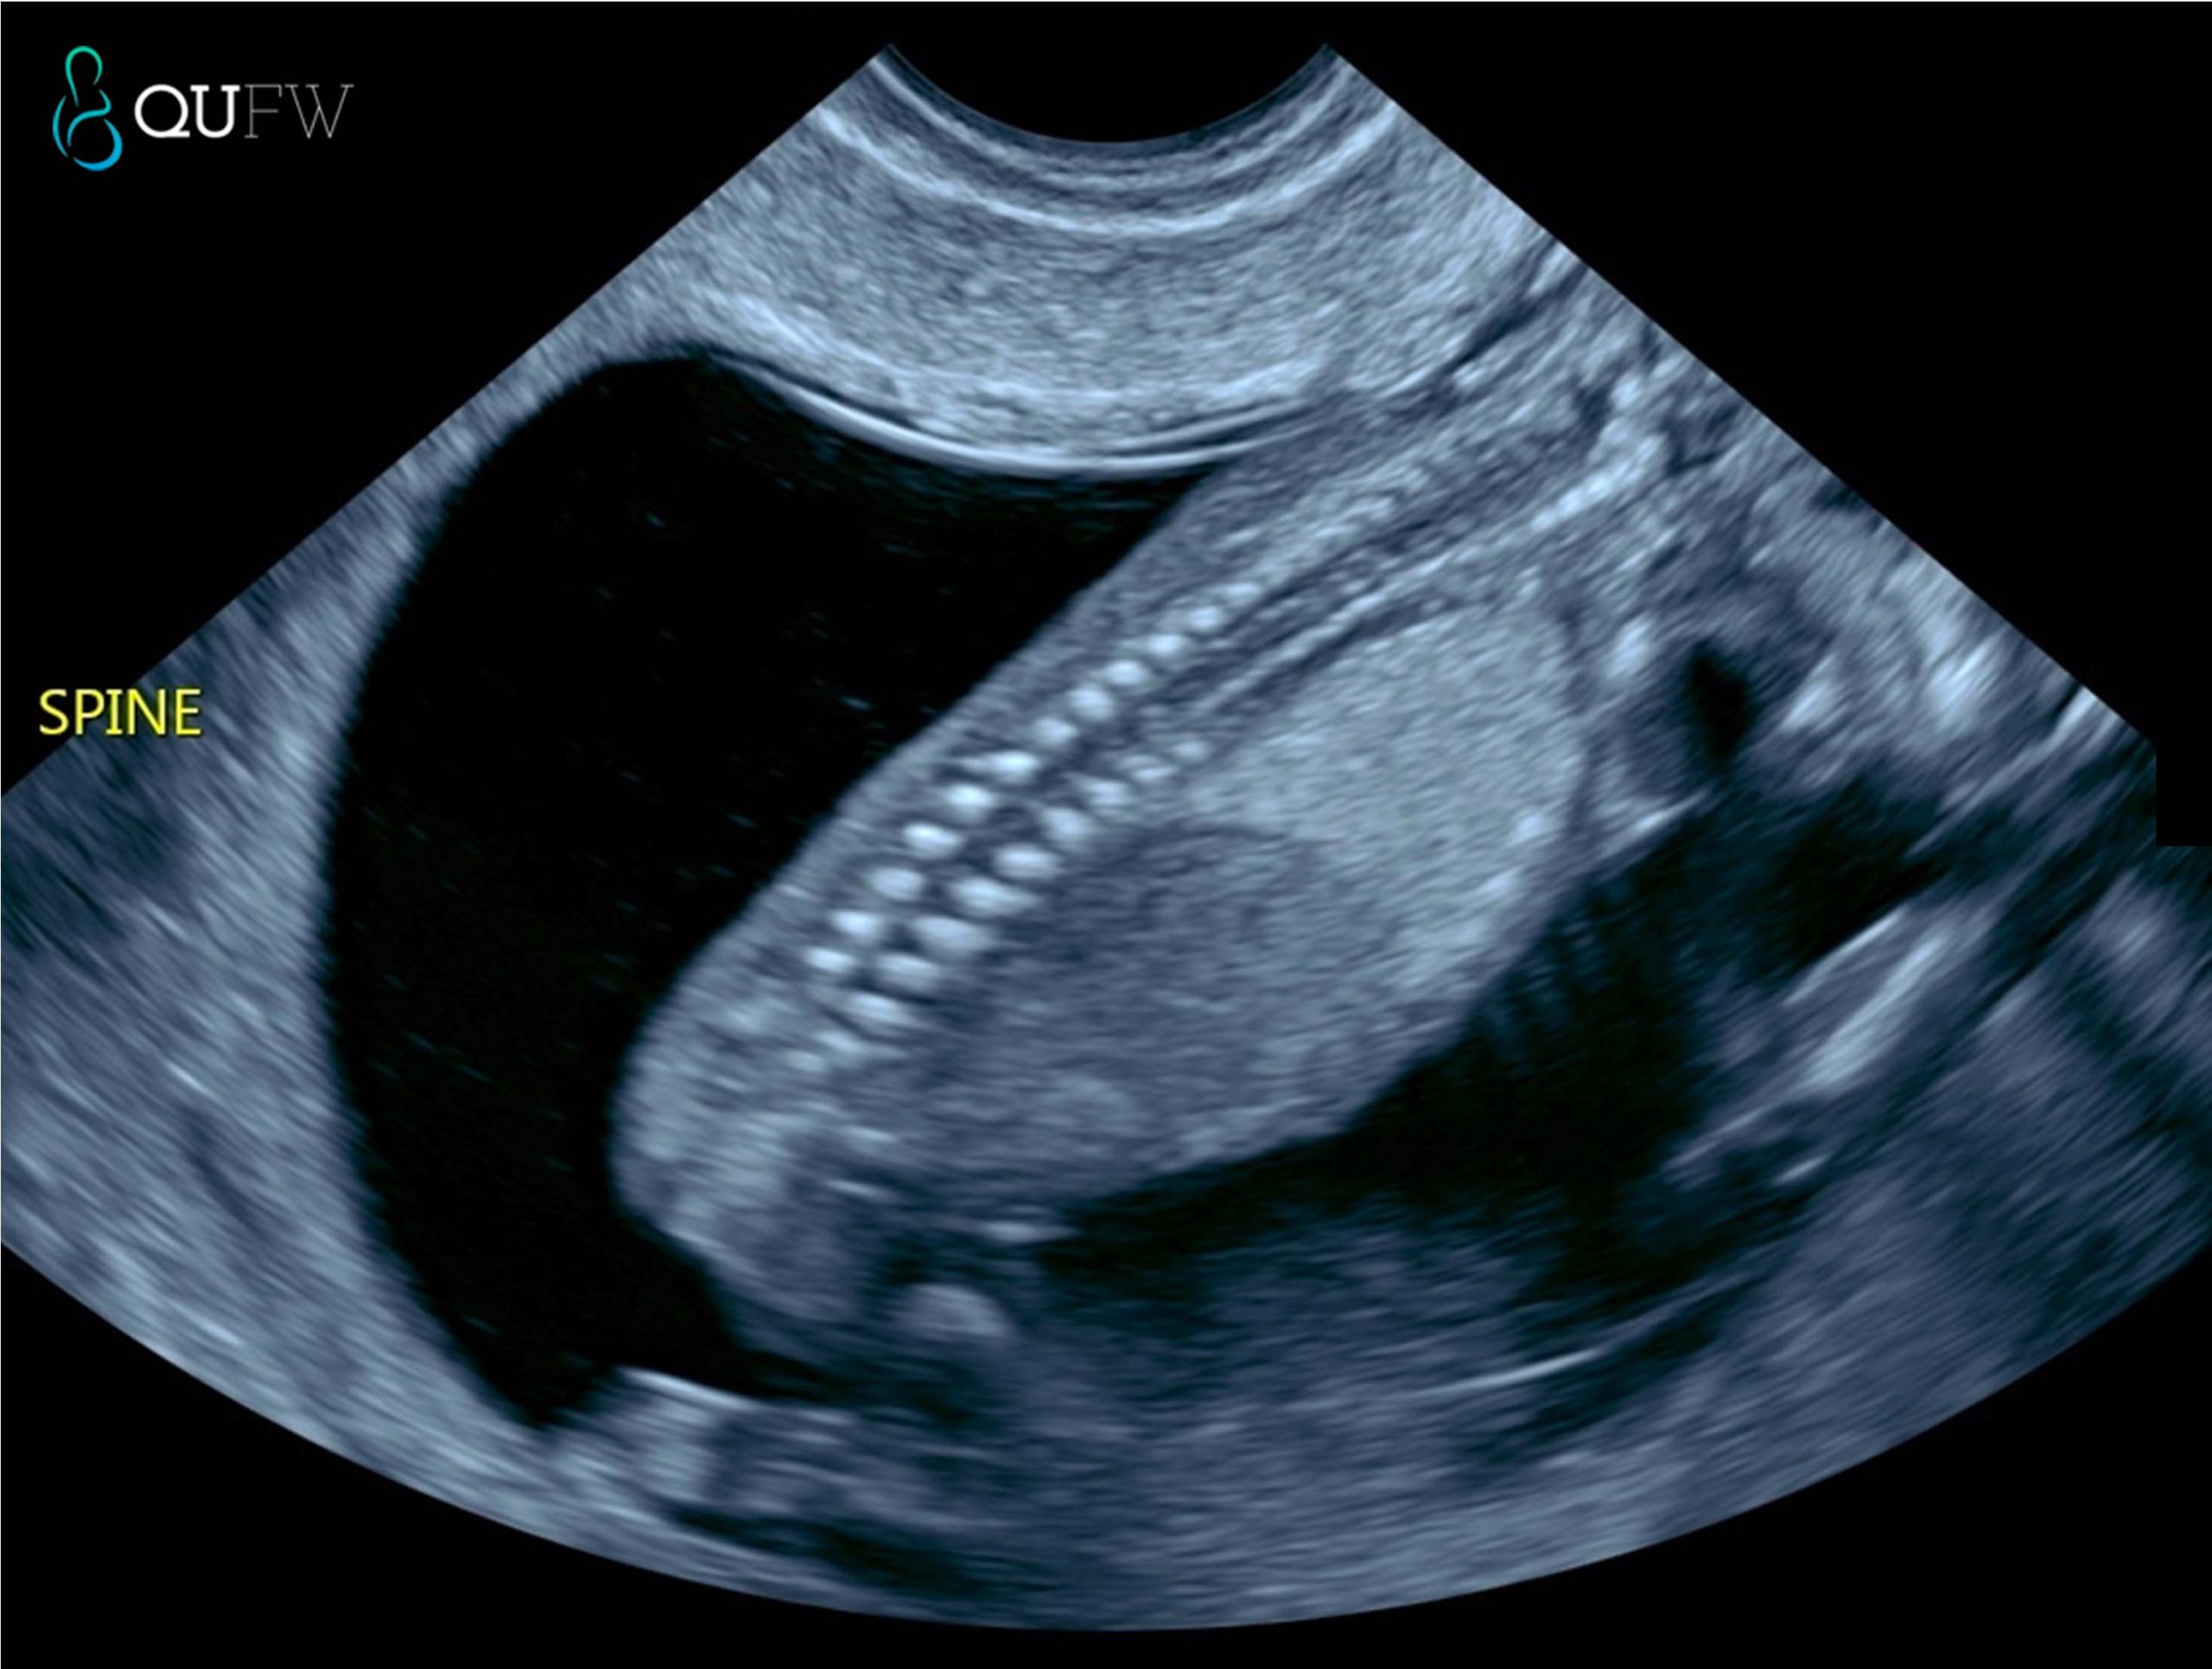

Finally, an early anatomy review is performed, allowing a first assessment of the brain, face, heart, spine, abdomen, abdominal wall, limbs, and other structures. While detailed anatomy scans follow later in pregnancy, this early survey can sometimes detect major abnormalities, giving families and clinicians valuable information sooner.

Early structural assessment of the spine